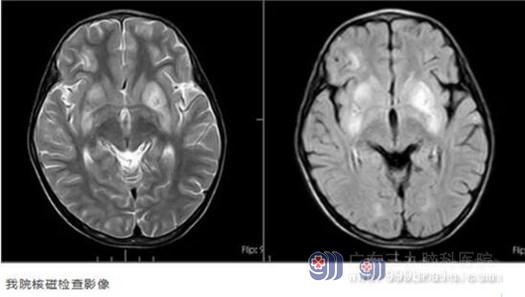

住院期间,我院头颅MR检查回报:双侧基底节区、双侧额叶及左侧颞顶叶多发病变,脑膜可疑强化。视频脑电图结果:1.背景节律异常;2.癫痫样放电,右侧中央区及CZ。